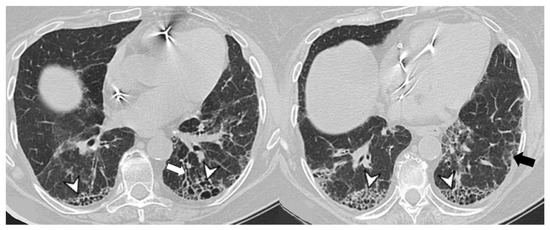

4.2.2. HRCT Findings of Patients with Anti-MDA-5 Abs

| Lesions | GGO, reticulations, consolidations | consolidations, GGOs | |

| Distribution | Homogeneous; lower lung lobes, along bronchovascular bundles and lung periphery; loss of volume of lower lobes | Patchy; peripheral lower lobes or along the bronchovascular bundles | |

| CT pattern | NSIP OP NSIP-OP UIP DAD-unclassifiable | 50% 20% 25% 10% +/− | 20% 50% 25% <5% ++ |